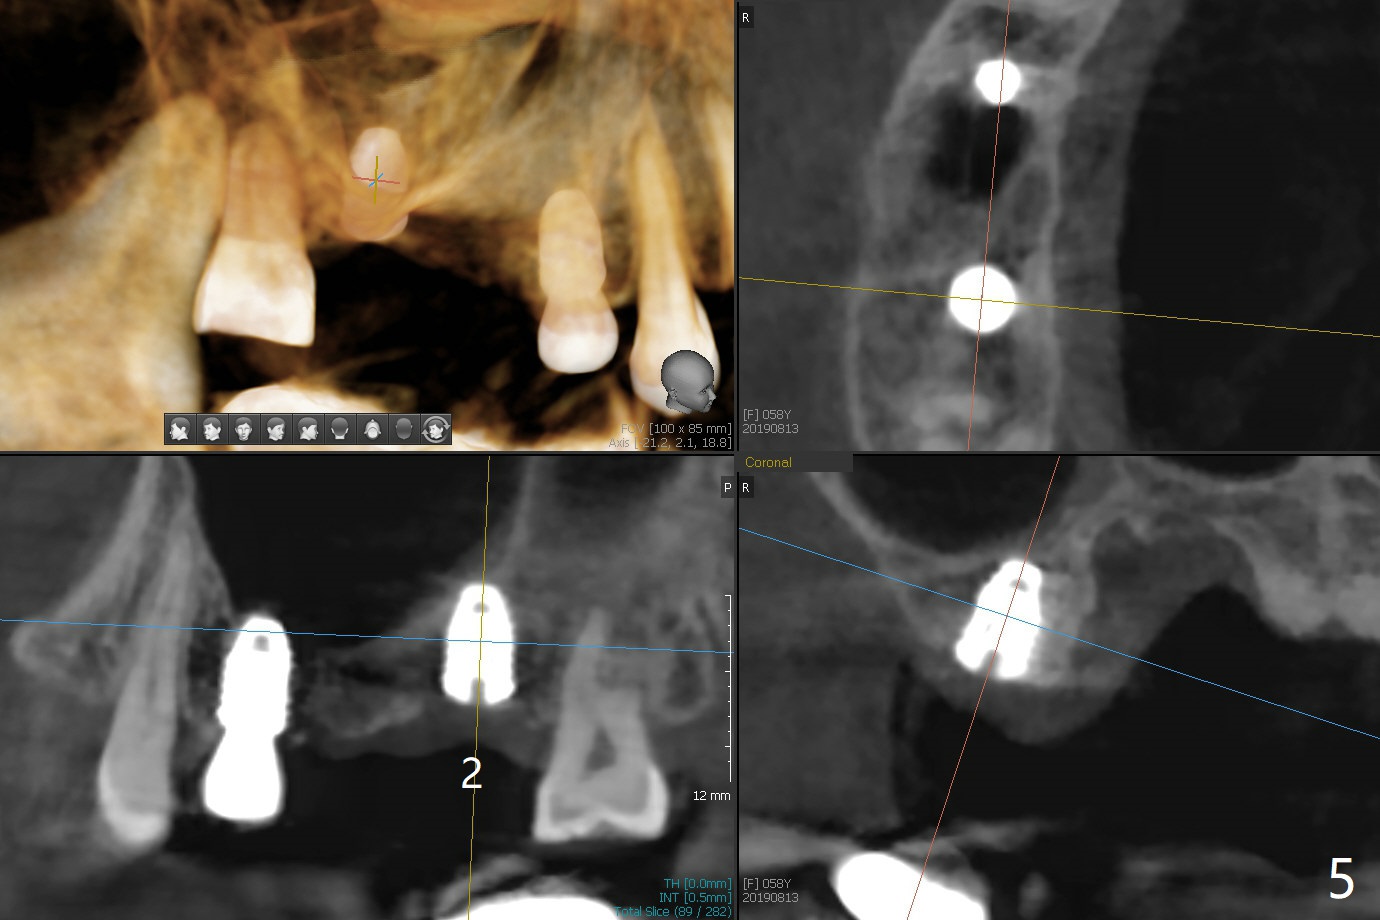

Eight months post socket preservation, the bone density at #2 feels low during osteotomy.  The site is underprep not only in depth, but also in diameter (4.0x7.3 mm with 10.5 mm offset), but a 5x7.3 mm implant is ~ 1 mm shy of the purposed depth.  Following 4.5x7.3 and 4.0x8.5 mm drills (without air leak), the implant reaches the depth, but with ~ 5 Ncm insertion torque (Fig.1).  Placement of the same sized implant at #4 (healed site) is smooth with satisfactory stability (~30 Ncm, Fig.2,3).  Ideally the site of #2 should have been prepared with sinus lift so that the apex of a longer implant would be engaged to the sinus floor for stability.  These two implants heal normally clinically and radiographically 1.5 months postop (Fig.4-6).  Bone surrounds the implant at #2 when it is uncovered 4 months postop (Fig.7).  The retainer at #4 looks short with large gingival embrasure (Fig.8 *) 6.5 months postop.  Finally the patient is ok with it because she does not like gingivectomy.  Provisional should have fabricated (Fig.9 light yellow curved lines) to create gingival scallops with secondary formation of papillae (arrows).